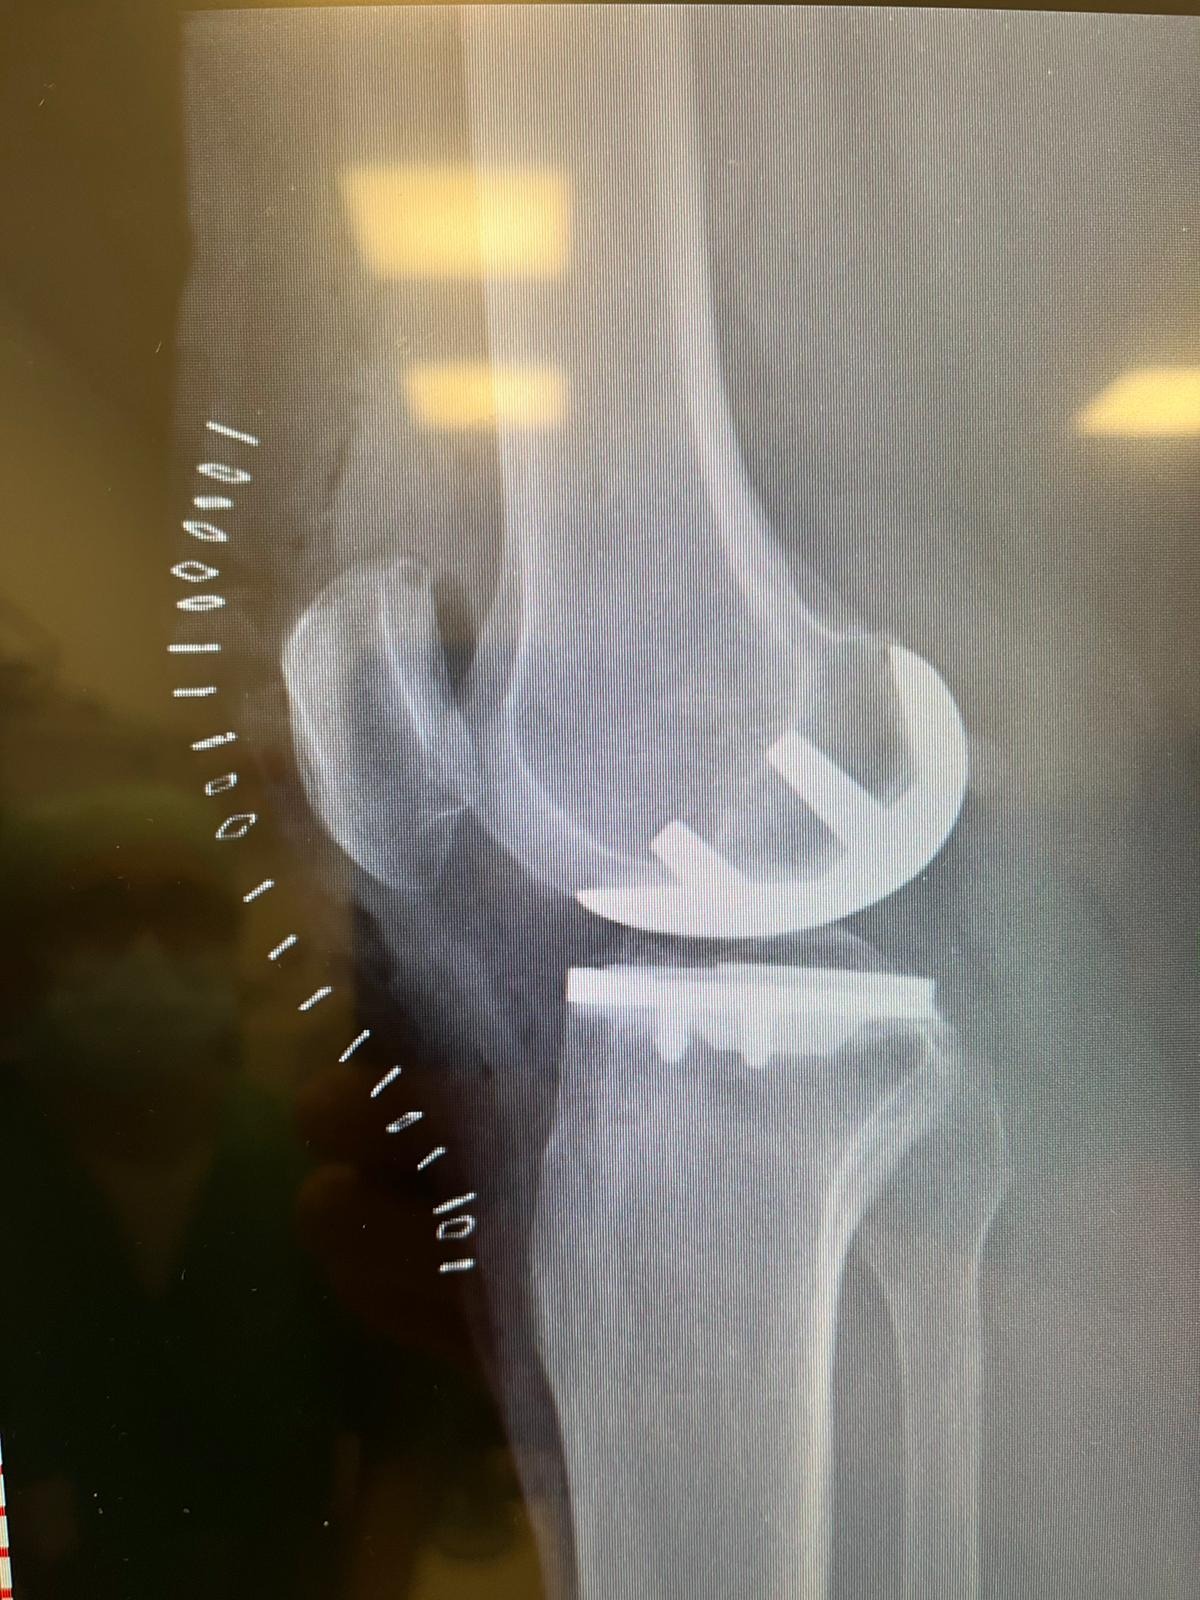

Protesi Monocompartimentale

Se l'usura riguarda solo una parte del ginocchio, procediamo con la sostituzione esclusiva del "settore" danneggiato. Questo ci permette di conservare i tuoi legamenti crociati e tutto l'osso sano, garantendoti un recupero rapido e mantenendo intatta la sensazione del tuo ginocchio naturale.

La rivoluzione della Protesi Totale: Allineamento Cinematico e design "Medial Pivot"

Per decenni, la chirurgia protesica ha seguito una regola fissa: "raddrizzare" il ginocchio di tutti i pazienti allo stesso modo, come se fossimo tutti fatti con lo stampino. Oggi, grazie all'Allineamento Cinematico, abbiamo ribaltato questo concetto. Invece di forzare la tua gamba ad adattarsi a una protesi standard geometrica, adattiamo la protesi all'esatta forma e inclinazione che il tuo ginocchio aveva prima di ammalarsi. È l'esatta differenza che c'è tra indossare un abito "taglia unica" e farsi cucire un vestito su misura da un sarto.

A questa filosofia personalizzata associamo l'utilizzo di impianti di altissima gamma con design Medial Pivot (a perno mediale). Il ginocchio umano, infatti, non si piega in modo meccanico come una semplice porta a cerniera. Mentre si flette, la parte esterna scivola all'indietro facendo "perno" sulla parte interna. Queste moderne protesi riproducono fedelmente questa sofisticata danza naturale.